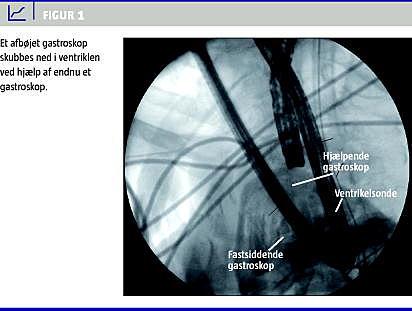

Ved anlæggelsen af ventrikelsonden begyndte patienten at hoste og forsøgte at rejse sig fra lejet. Herved afbøjede gastroskopet fra hiatusherniet ind i øsofagus. Ved fremføring af gastroskopet blev slyngen i ventriklen større, mens forsøg på tilbagetrækning fik spidsen af gastroskopet til at glide oralt, og denne var til sidst beliggende ved larynx. Der blev tilkaldt assistance af en kollega og ved hjælp af endnu et gastroskop samt gennemlysning lykkedes det at skubbe det første gastroskop ned i ventriklen, hvorefter det kunne fjernes (Figur 1 ).

Risikoen for, at gatroskopet kommer på afveje, forøges, når patienten har hiatushernie, idet gastroskopet så kan sidde fast i både herniet og øsofagus [3]. Holdes der god afstand til cardia ved inspektion af fundus, kan man mindske risikoen, for at gastroskopet indeklemmes. Man skal desuden sørge for, at gastroskopet er rettet helt ud ved tilbageføring til øsofagus [4]. Ved et fastsiddende gastroskop er den første handling at fremføre gastroskopet, så spidsen igen falder ind i ventriklen. Er dette ikke muligt, kan man som beskrevet i sygehistorien benytte endnu et gastroskop samt gennemlysning, når spidsen skal skubbes ned i ventriklen. En løsning, hvor gastroskopet trækkes op gennem øsofagus, mens det ligger dobbelt [5], kan ikke anbefales på grund af risikoen for perforation af øsofagus.